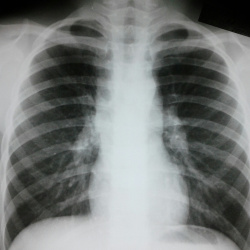

Молодой человек 22 года. Профилактическое обследование. Пациента не видел. Не нравится указанное стрелочкой место. Что может быть